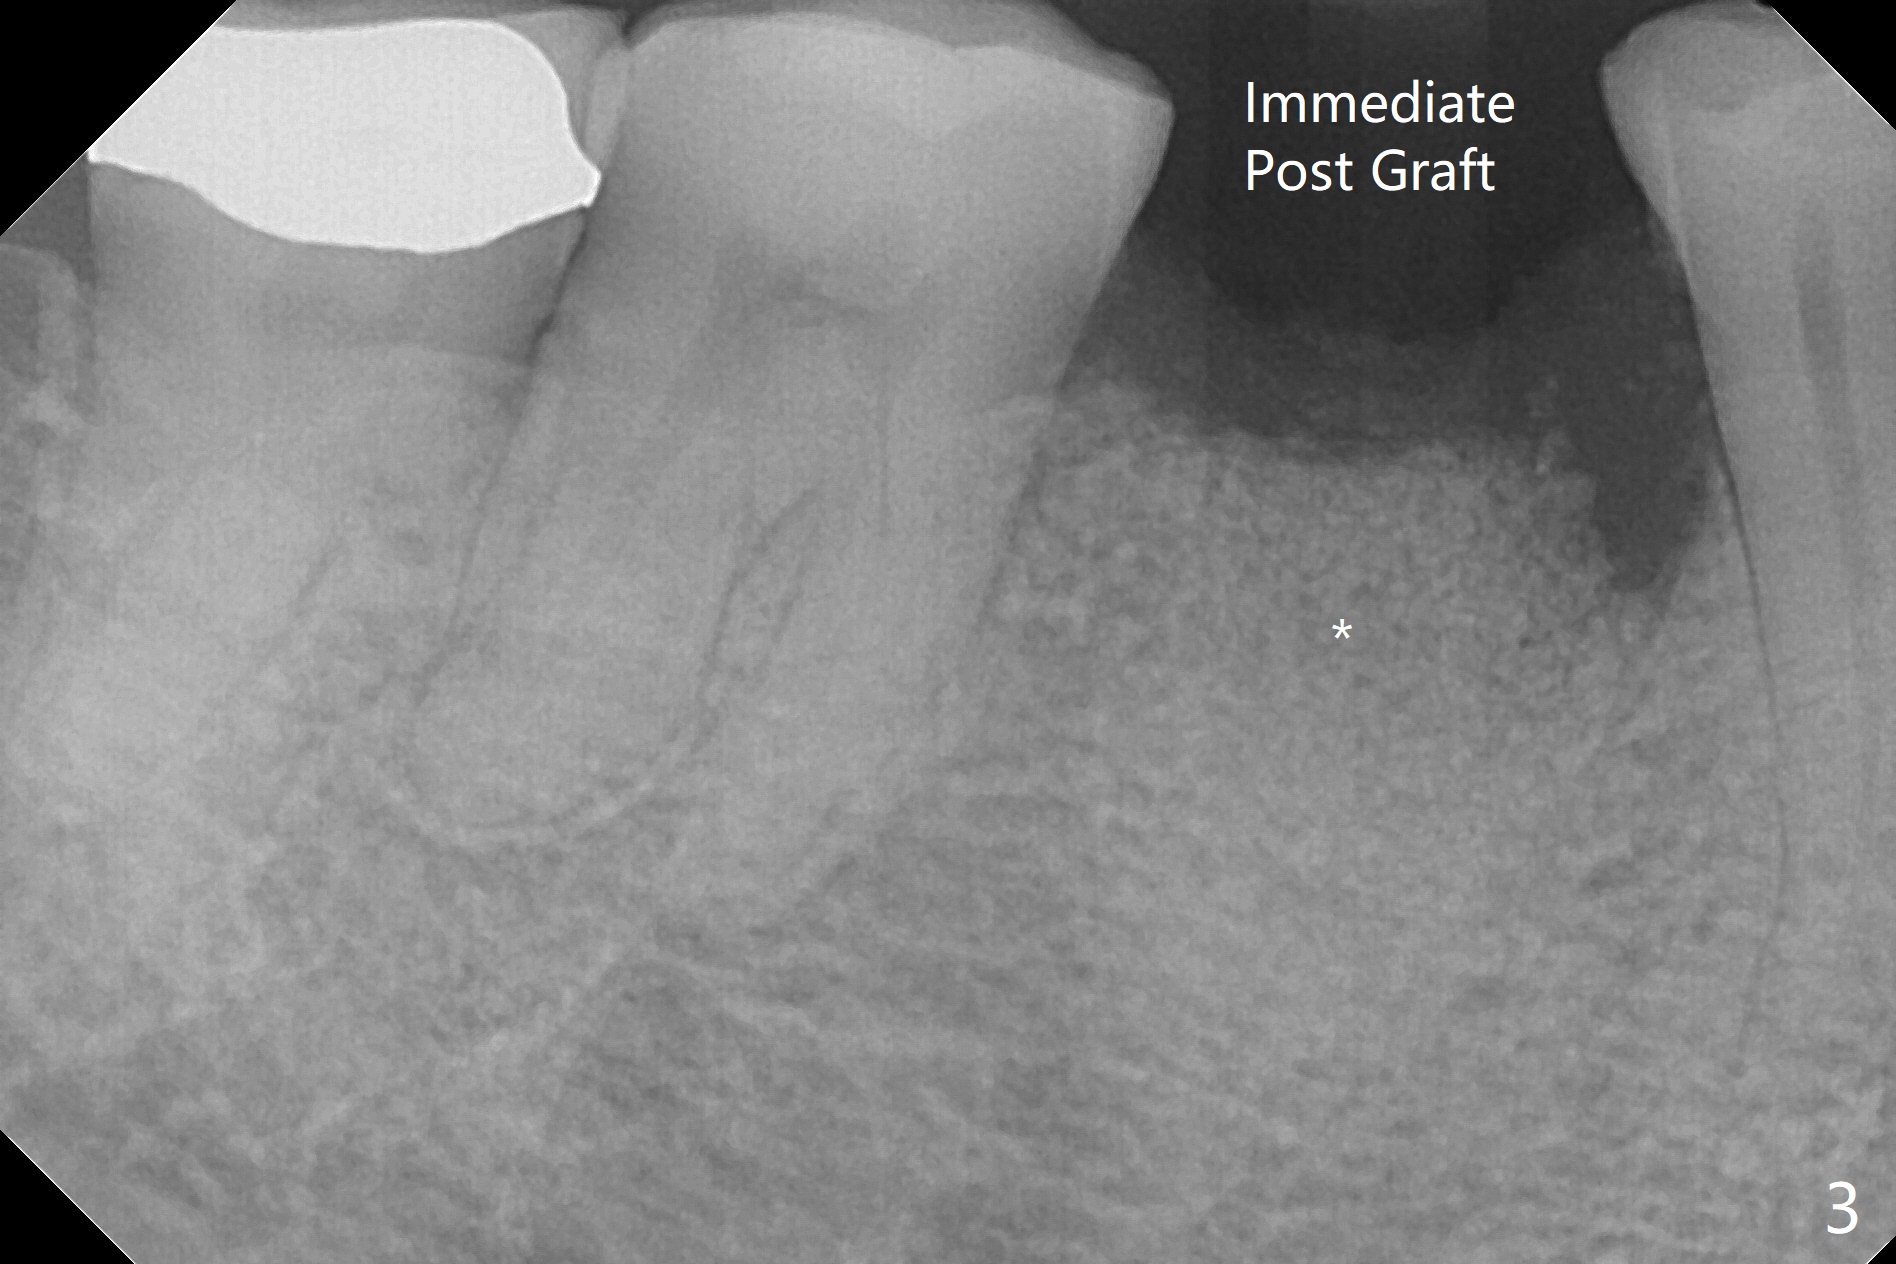

A 77-year-old woman agrees to have the lower right 2nd premolar extracted after lengthy delay (Fig.1,2 buccolingual plate present, but low) and grafted (Fig.3 *).  Cortical graft is heavily packed, covered by a small piece of 6-month membrane and sutured with 4-0 Chromic gut suture.  The socket is closed 7 days postop (Fig.4).   The buccal plate seems to have been reformed 6 months postop (Fig.5,7, as compared to Fig.6 (pre-fracture)).  Return to No Deviation Surgery  Xin Wei, DDS, PhD, MS 1st edition 08/19/2020, last revision 05/12/2021